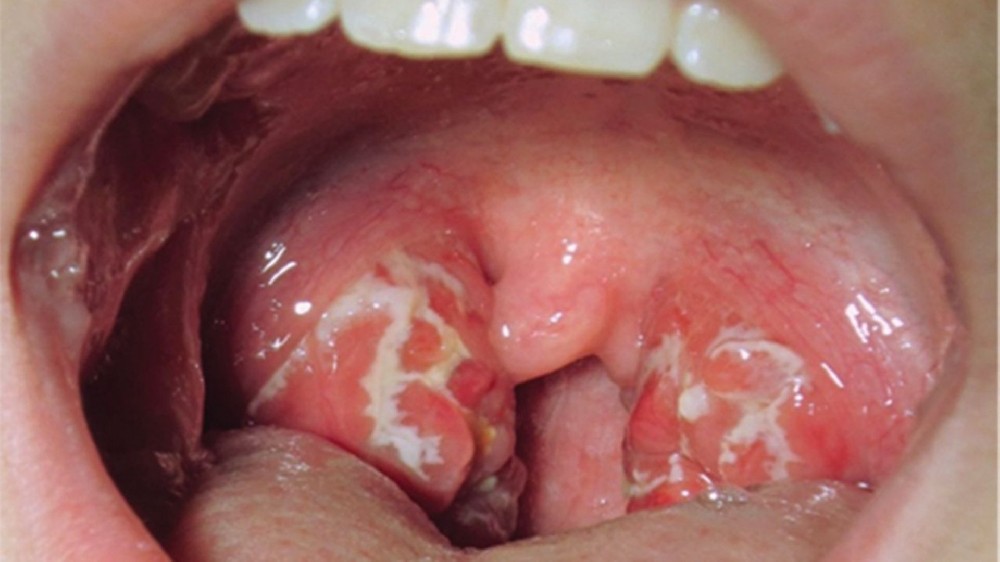

口咽癌(喉癌)是發生在口咽組織的侵襲性癌症,口咽組織包括扁桃腺、軟顎、舌根和咽壁。這種癌症主要是內層的鱗狀細胞發生惡性變化。每年全球有數以千計的人被診斷出罹患口咽癌(喉癌),對他們的生活品質和情緒健康造成深遠的影響。瞭解此種疾病可增強患者和家屬的能力,並透過明智的治療選擇和早期檢測,為他們帶來希望。

口咽癌(喉癌)的症狀

認識口咽癌(喉癌)的早期症狀可確保及時診斷,增加成功治療的機會。根據疾病的階段和腫瘤在喉嚨或口咽部結構內的位置,症狀會有很大的差異。

口咽癌(喉癌)早期症狀

疼痛或無痛的持續性喉嚨痛持續兩週以上

感覺喉嚨或頸部有腫塊,且無法自然消退

吞嚥困難(吞嚥困難),尤其是固體食物

聲音明顯改變或持續性聲音沙啞

慢性咳嗽,有時伴有微量帶血的痰液

共用神經通路導致的耳痛(轉介性耳痛)

不明原因的體重下降和食慾不振

當發現上述一種或多種症狀時,應立即進行醫療評估,以排除口咽癌(喉癌)的可能性,或在早期階段尋求有效的治療。早期發現和即時介入對於確保患者的最佳療效和長期康復至關重要。